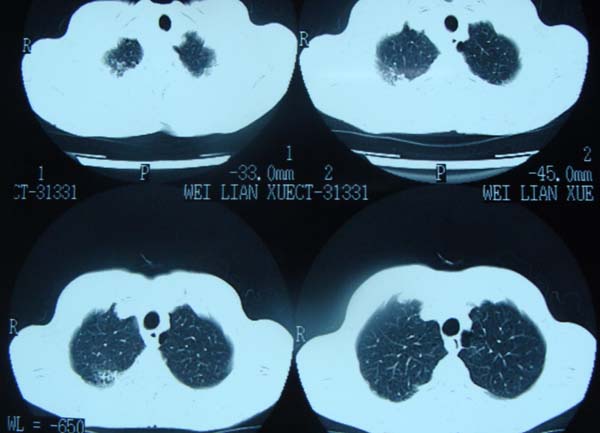

以下是引用pujunzhi在2009-6-21 21:48:00的发言:[br]右肺上叶后段见一空洞性病灶,灶周有渗出即晕征,右肺门肿大---可考虑感染性空洞和癌性空洞,先抗炎抗痨后复查并完善相关检查。有癌性空洞伴肺门淋巴结转移的可能。